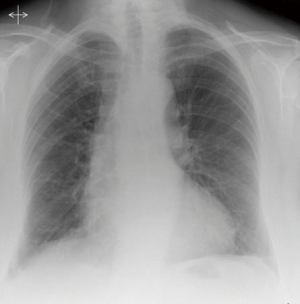

A CT-guided biopsy (Figure 1B) was performed following multidisciplinary discussion, confirming a parathyroid adenoma on histology. The patient developed a right sided apical pneumothorax following the biopsy which was managed with a chest drain, and she was discharged. She was readmitted after one week, with a 3-day history of progressive shortness of breath but was hemodynamically stable. A repeat CT scan showed a large right pleural effusion (Figure 2) with no active contrast extravasation.

Figure 2 Post-biopsy CT showing a large right sided hemothorax. A large right sided hemothorax is seen to occupy most of the pleural cavity. The mediastinal tumor is seen to the right of the trachea, with evidence of tracheal deviation and mediastinal shift.